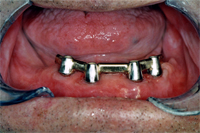

Am 2. Oktober 2006 wurden unter Aufklappung vier Implantate gesetzt. Eine Woche später kommt der Patient zur Nahtentfernung (Abb. 1). Die postoperative Schwellung ist verschwunden und die Nähte werden entfernt. Die Einheilkappen sind für die Abdrucknahme vom Implantat entfernt (Abb. 2). Mit der bestehenden Prothese wird nun der Abdruck genommen. Noch gleichentags fertigt der Techniker den Implantatsteg an, den ich im Mund provisorisch festschraube (Abb. 3).

Zwei Monate später, am 12. Dezember 2006, habe ich die Unterkieferprothese unterfüttert und den Implantatsteg definitiv auf den Implantaten verschraubt (Abb. 5).